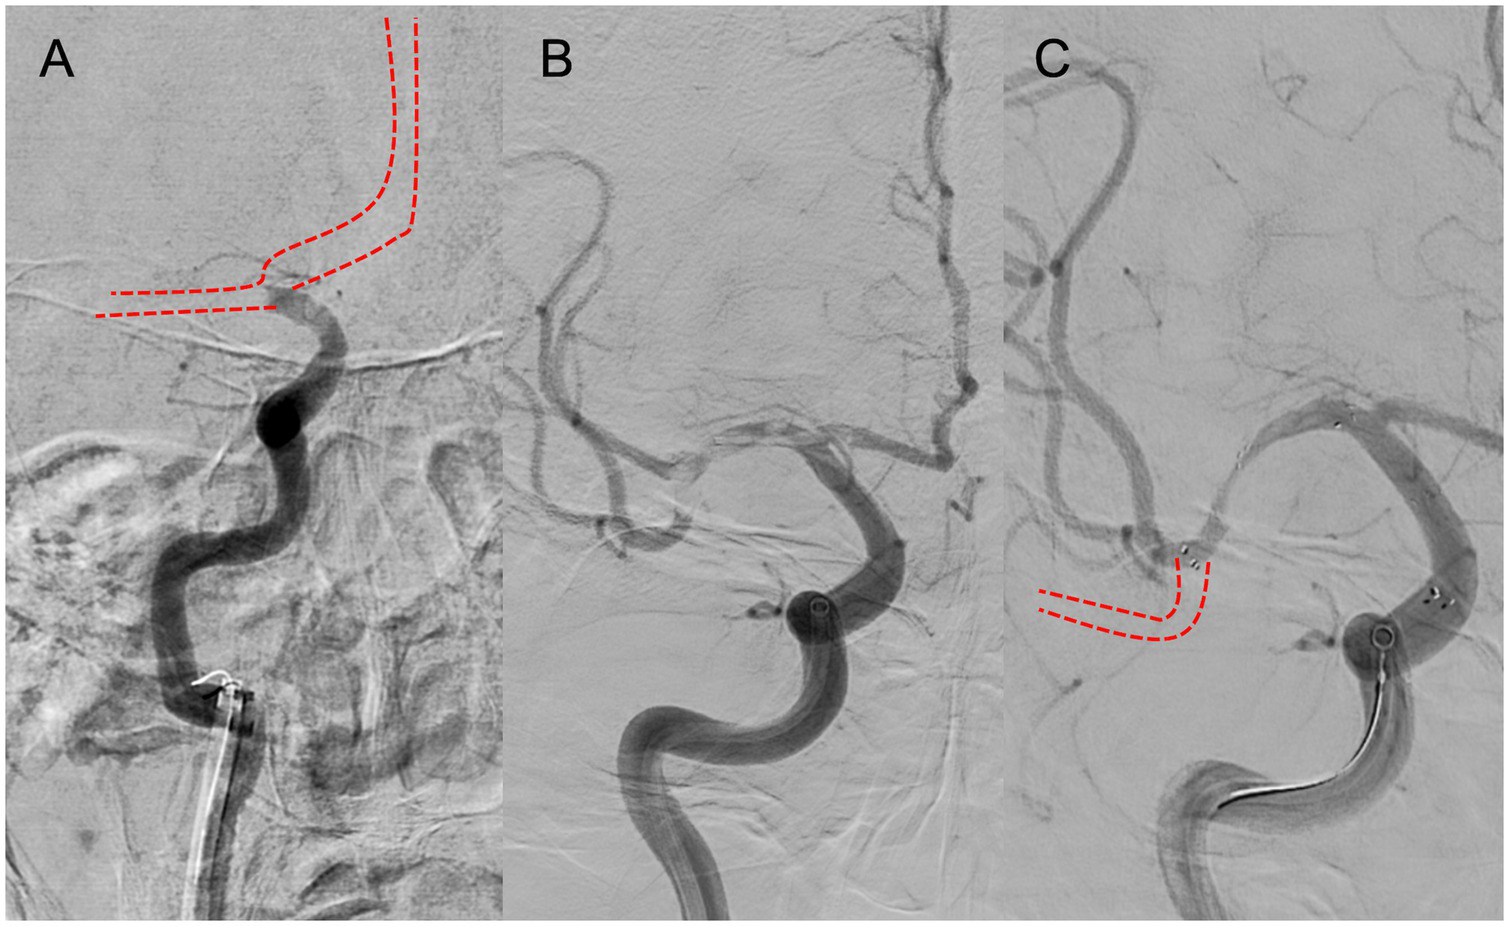

4.2. Branching-site and truncal-type occlusion

A multicenter observational study from Korea determined that occlusions of a truncal type were correlated with a lack of responsiveness to stent retrievers and were the fundamental cause of strokes (36). The subjects were patients undergoing MT for intracranial occlusions of the internal carotid artery, MCA, proximal MCA, intracranial vertebral artery, or basilar cerebral artery. The occlusions were classified as either branching-site occlusion or truncal-type occlusion. Branching-site occlusion was defined as at least one of the following three conditions (Figure 5); (1) anterior communicating artery collateral flow that could not proceed to the contralateral ICA or MCA because it involved the internal cerebral artery bifurcation site (T occlusion); (2) direct visualization of a Y-or T-shaped filling defect involving a bifurcation site (Y-or T-shaped clot); and (3) another branch could not be visualized or was only partially visualized when the retriever was deployed to a branch across the occlusion site. Truncal-type occlusion, on the other hand, was defined as all branches and bifurcations visible beyond the occluded vessel, including those observed at recanalization. After a comprehensive evaluation involving chest electrocardiogram, echocardiography, cardiac CT, and cervical vascular echocardiography, the patients were classified as having embolic or non-embolic LVO. Of the 259 patients (mean age 70.3 years; male/female ratio 132:127), 83.4% had embolic LVO. Multivariate analysis revealed that younger age, prior coronary artery disease, and truncal-type occlusion were independently linked to the absence of embolic LVO (OR, 9.07; 95% CI, 3.74–22.0). Furthermore, truncal-type occlusion was associated with a higher frequency of reocclusion and a longer time to recanalization during stent retriever treatment. In a subanalysis of this study, truncal-type occlusion was associated with 93% of ICAS-related LVO and 10% of embolic LVO (p < 0.01) (35), whereas branching-site occlusion was associated with 7% of ICAS-related LVO and 90% of embolic LVO. In a separate study among 115 LVO patients in China, truncal-type occlusion was present in 93% of ICAS-related LVO and 10% of embolic LVO, while branching-site occlusion was observed in 7% of ICAS-related LVO and 90% of embolic LVO, yielding a significant difference between the two LVO types (p < 0.01 for each). The area under the curve of ICAS-related LVO in truncal-type occlusion was 0.916, with the sensitivity of 92.86% and specificity of 90.41% (36). CT angiography can also assess truncal-type occlusion, and although it is not a direct predictor of pathogenesis, branching-site occlusion as determined by CT angiography has been reported to independently predict the success of recanalization with stent retrievers (OR, 8.20; 95% CI, 3.45–19.5) (37). Representative cases of truncal-type occlusion/branching-site occlusion are shown in Figure 6.

Figure 5

Branching-site occlusion. (A) Intracranial carotid artery occlusion without visualization of the anterior communicating artery (IC-T occlusion). (B) Y- or T-shaped visualization defect including vessel branches. (C) Partial or complete lack of visualization of vessel branches on angiography after stent retriever deployment.